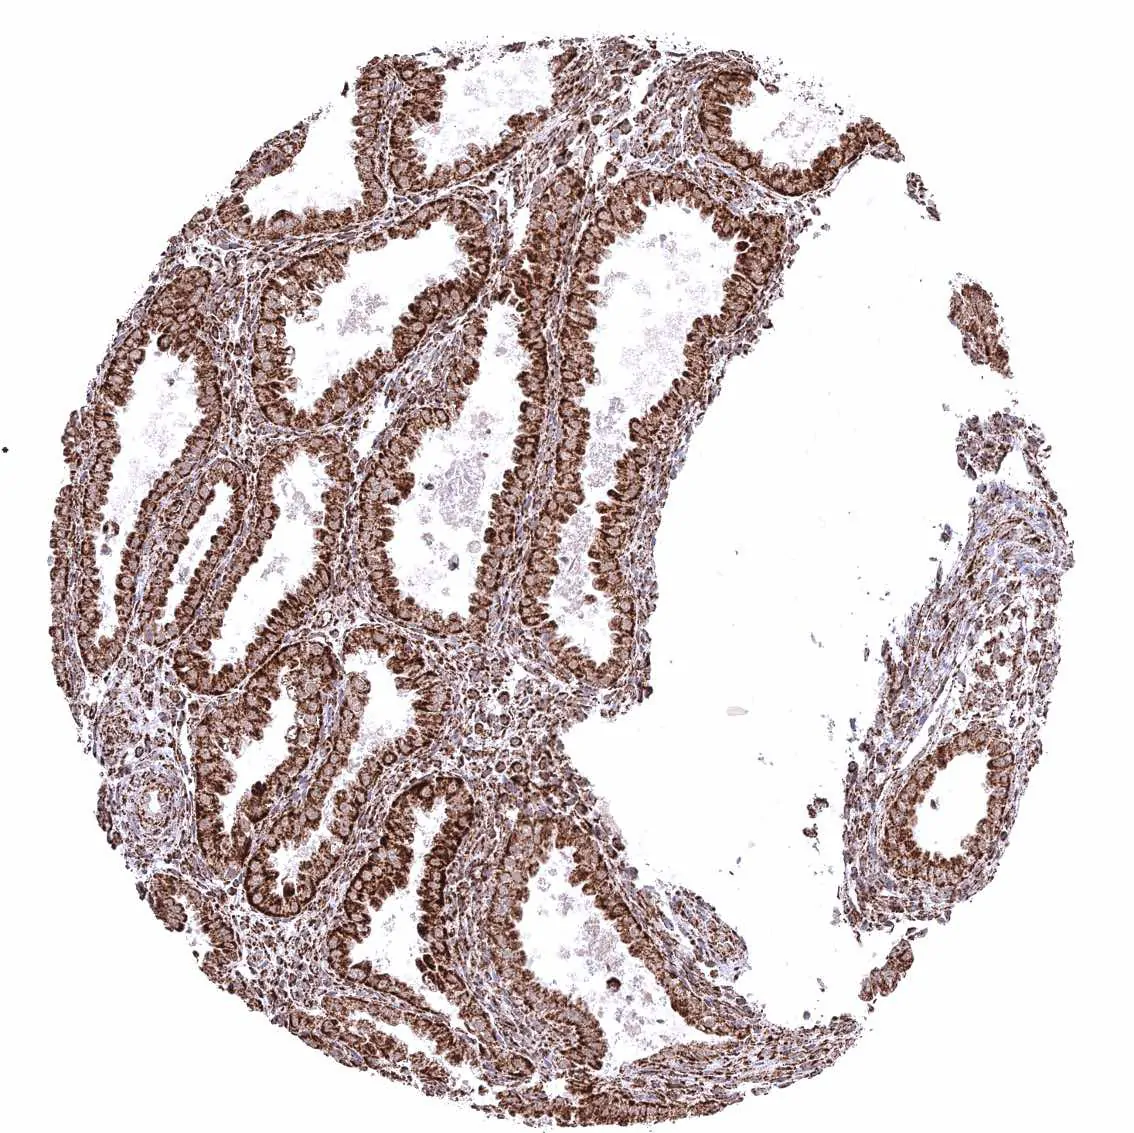

Pancreas – Distinct granular, perinuclear, cytoplasmic ATP5J staining in all cell types. Some cells with higher staining intensity may be related to the excretory system.